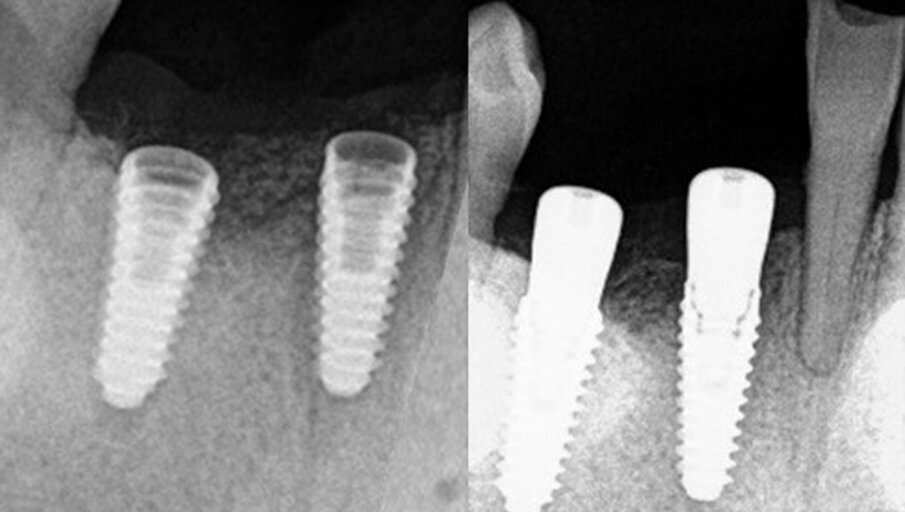

The surgical stent was soaked in povidone-iodine prior to use surgically. Chlorhexidine may be used as an alternative liquid to disinfect the guide. Local anaesthetic was administered, and the surgical guide verified for fit and stability intra-orally (Figs. 12a & b). A crestal incision was made with a scalpel, and a full-thickness flap was reflected to expose the crest. The Guide Right surgical guide with 4 mm guide sleeves was inserted. The osteotomies were initiated with a 2.2 mm drill in a 2.3 mm insert and completed with Densah osseodensification burs (Versah), starting at 2.5 mm and continuing to 3.5 mm in diameter to a depth of 11.5 mm at both sites through the surgical guide (Fig. 13). A 3.5 × 11.5 mm implant was placed into the central incisor site and a 4.0 × 11.5 mm implant was inserted into the canine site (AnyRidge, MegaGen). A post-insertion radiograph was taken (Fig. 14a). Cover screws were placed on both implants, and the flap was secured with sutures.

Owing to the pandemic and shutdown, a delay in the return of the patient to initiate the prosthetic stage of treatment resulted. When the patient returned, the implants were exposed with a split-thickness flap. An implant stability quotient value of 80 was recorded for the central incisor implant and of 84 for the canine implant, and healing abutments were placed. A radiograph was taken to check the status of the implants (Fig. 14b). An open-tray impression was captured, opposing impressions taken and a maxillomandibular relationship record taken. Healing abutments were replaced, and the impressions were sent to the laboratory for fabrication of the prosthesis.

Fig. 13: Densah osseodensication drills used through the Guide Right surgical guide to create the osteotomies for the implants to be placed.

Figs. 14a & b: Periapical radiographs of the implant placement (a) and healing abutments placed (b).